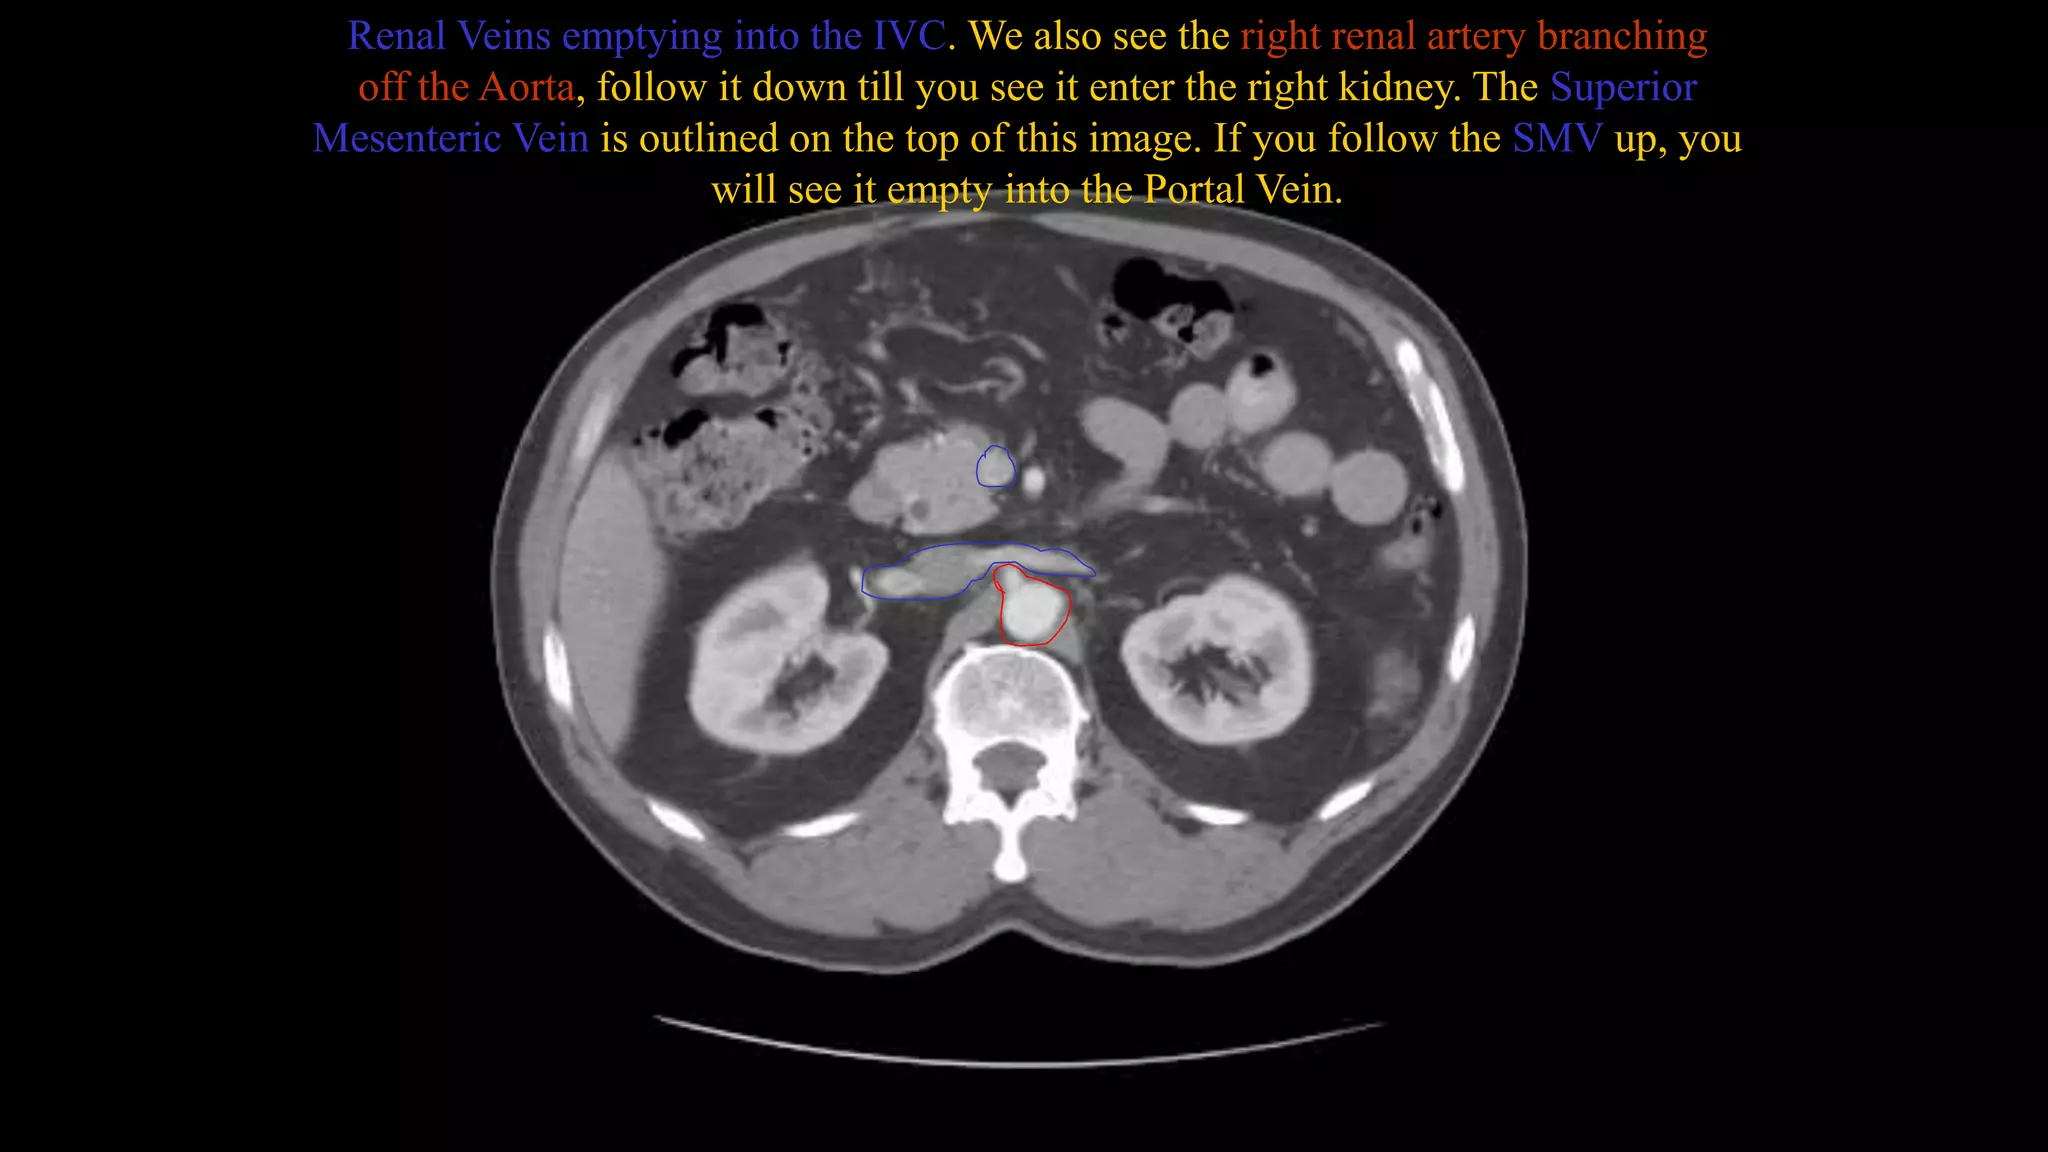

Renal Veins emptying into the IVC. We also see the right renal artery branching

off the Aorta, follow it down till you see it enter the right kidney. The Superior

Mesenteric Vein is outlined on the top of this image. If you follow the SMV up, you

will see it empty into the Portal Vein.

Renal Veins emptyinginto the IVC. We also see the right renal artery branching off the Aorta, follow it down till you see it enter the right kidney. The Superior Mesenteric Vein is outlined on the top of this image. If you follow the SMV up, you will see it empty into the Portal Vein.